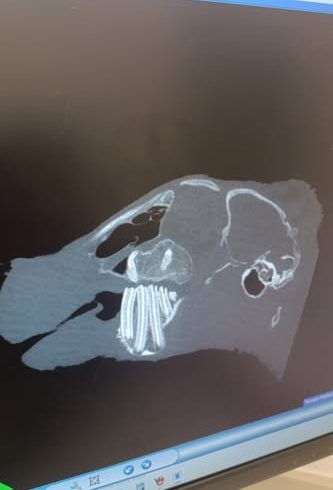

Vor einem Jahr kam sie zusammen mit ihrer Schwester zu uns. Ihre Schwester, die extrem klein war, ist bereits kurz darauf verstorben. Durch Inzucht hat auch Florea verschieden Baustellen. Sie ist kleinwüchsig, hat das Fell eines Babykaninchens und extreme Zahnfehlstellungen. Alle zwei Wochen mussten wir die Schneidezähne korrigieren, immer würde über einen OP zum Entfernen der Schneidezähne nachgedacht, aber sowohl wir als auch der Tierarzt hatten Bedenken wegen der Narkose. Vor 2 Monaten aber kamen wir um die OP nicht mehr herum und ihr wurden die oberen Schneidezähne sowie die oberen rechten Backenzähne entfernt. Sie hat die Narkose gut überstanden, hatte aber nach der Operation mit hartnäckigem Eiter zu kämpfen. Nach 4 Wochen war dann endlich alles gut verheilt. Nun kam vorletzte Woche der Eiter zurück und unser Tierarzt empfahl uns, ein Wach-CT machen zu lassen um zu sehen, was da los ist. Letzte Woche Montag war es dann soweit und die Ergebnisse sind niederschmetternd. Zwei ihrer oberen Backenzähne sind nachgewachsen, sie hat außerdem eine Verdichtung am rechten Jochbein, entweder durch eine starke Entzündung oder durch einen Tumor, dafür muss erst eine Probe entnommen werden. Auch die Nase ist auf Höhe des linken entfernten Schneidezahns verdichtet, auch hier muss nochmal aufgemacht werden. Die Ärztin ist in ihrer Prognose sehr vorsichtig und macht uns keine großen Hoffnungen. Auch unser Tierarzt sieht das so, er geht auch eher von einem Tumor aus, da sich Floreas Haut und Fell verändern. Nichtsdestotrotz wollen wir ihr eine Chance geben, der Termin für die zweite OP steht und danach wissen wir dann mehr. Sie wird nicht alt werden, aber ein bisschen Zeit hätte sie schon noch verdient!